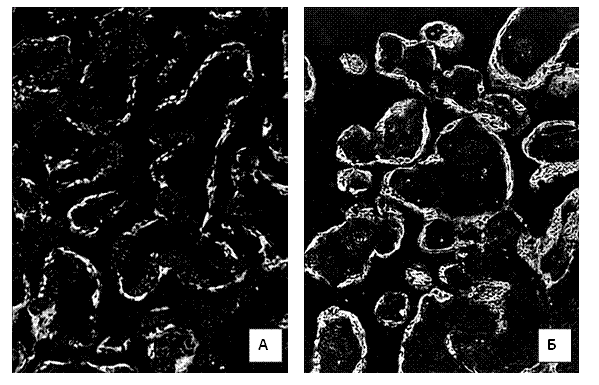

Рис.1. Світіння цитоплазми трофобласта хоріальних

ворсинок після обробки люмінолом при довжині хвилі 425 нм. А) контрольна група.

39 тижнів вагітності. Б) залізодефіцитна анемія. 39 тижнів вагітності.

Мікроскоп ЛЮМАМ-8. Об.20х.

Ок.10х.

При строкових пологах (37-40 тижнів гестації) інтенсивність світіння

цитоплазми трофобласта хоріальних ворсин після обробки люмінолом було вищим,

ніж у попередні терміни вагітності. У групі контролю середня інтенсивність

світіння була оцінено у 184,1±4,27. Однак, це світіння набувало рис вираженого

фракціонування по площі цитоплазми . При ЗДАВ світіння було оцінено в 204±5,71,

а фракціонування по площі цитоплазми, такого, як у групі контролю не

відмічалося. Різниця між групами дослідження за критерієм Mann-Whitney була

вірогідною (p<0,001).